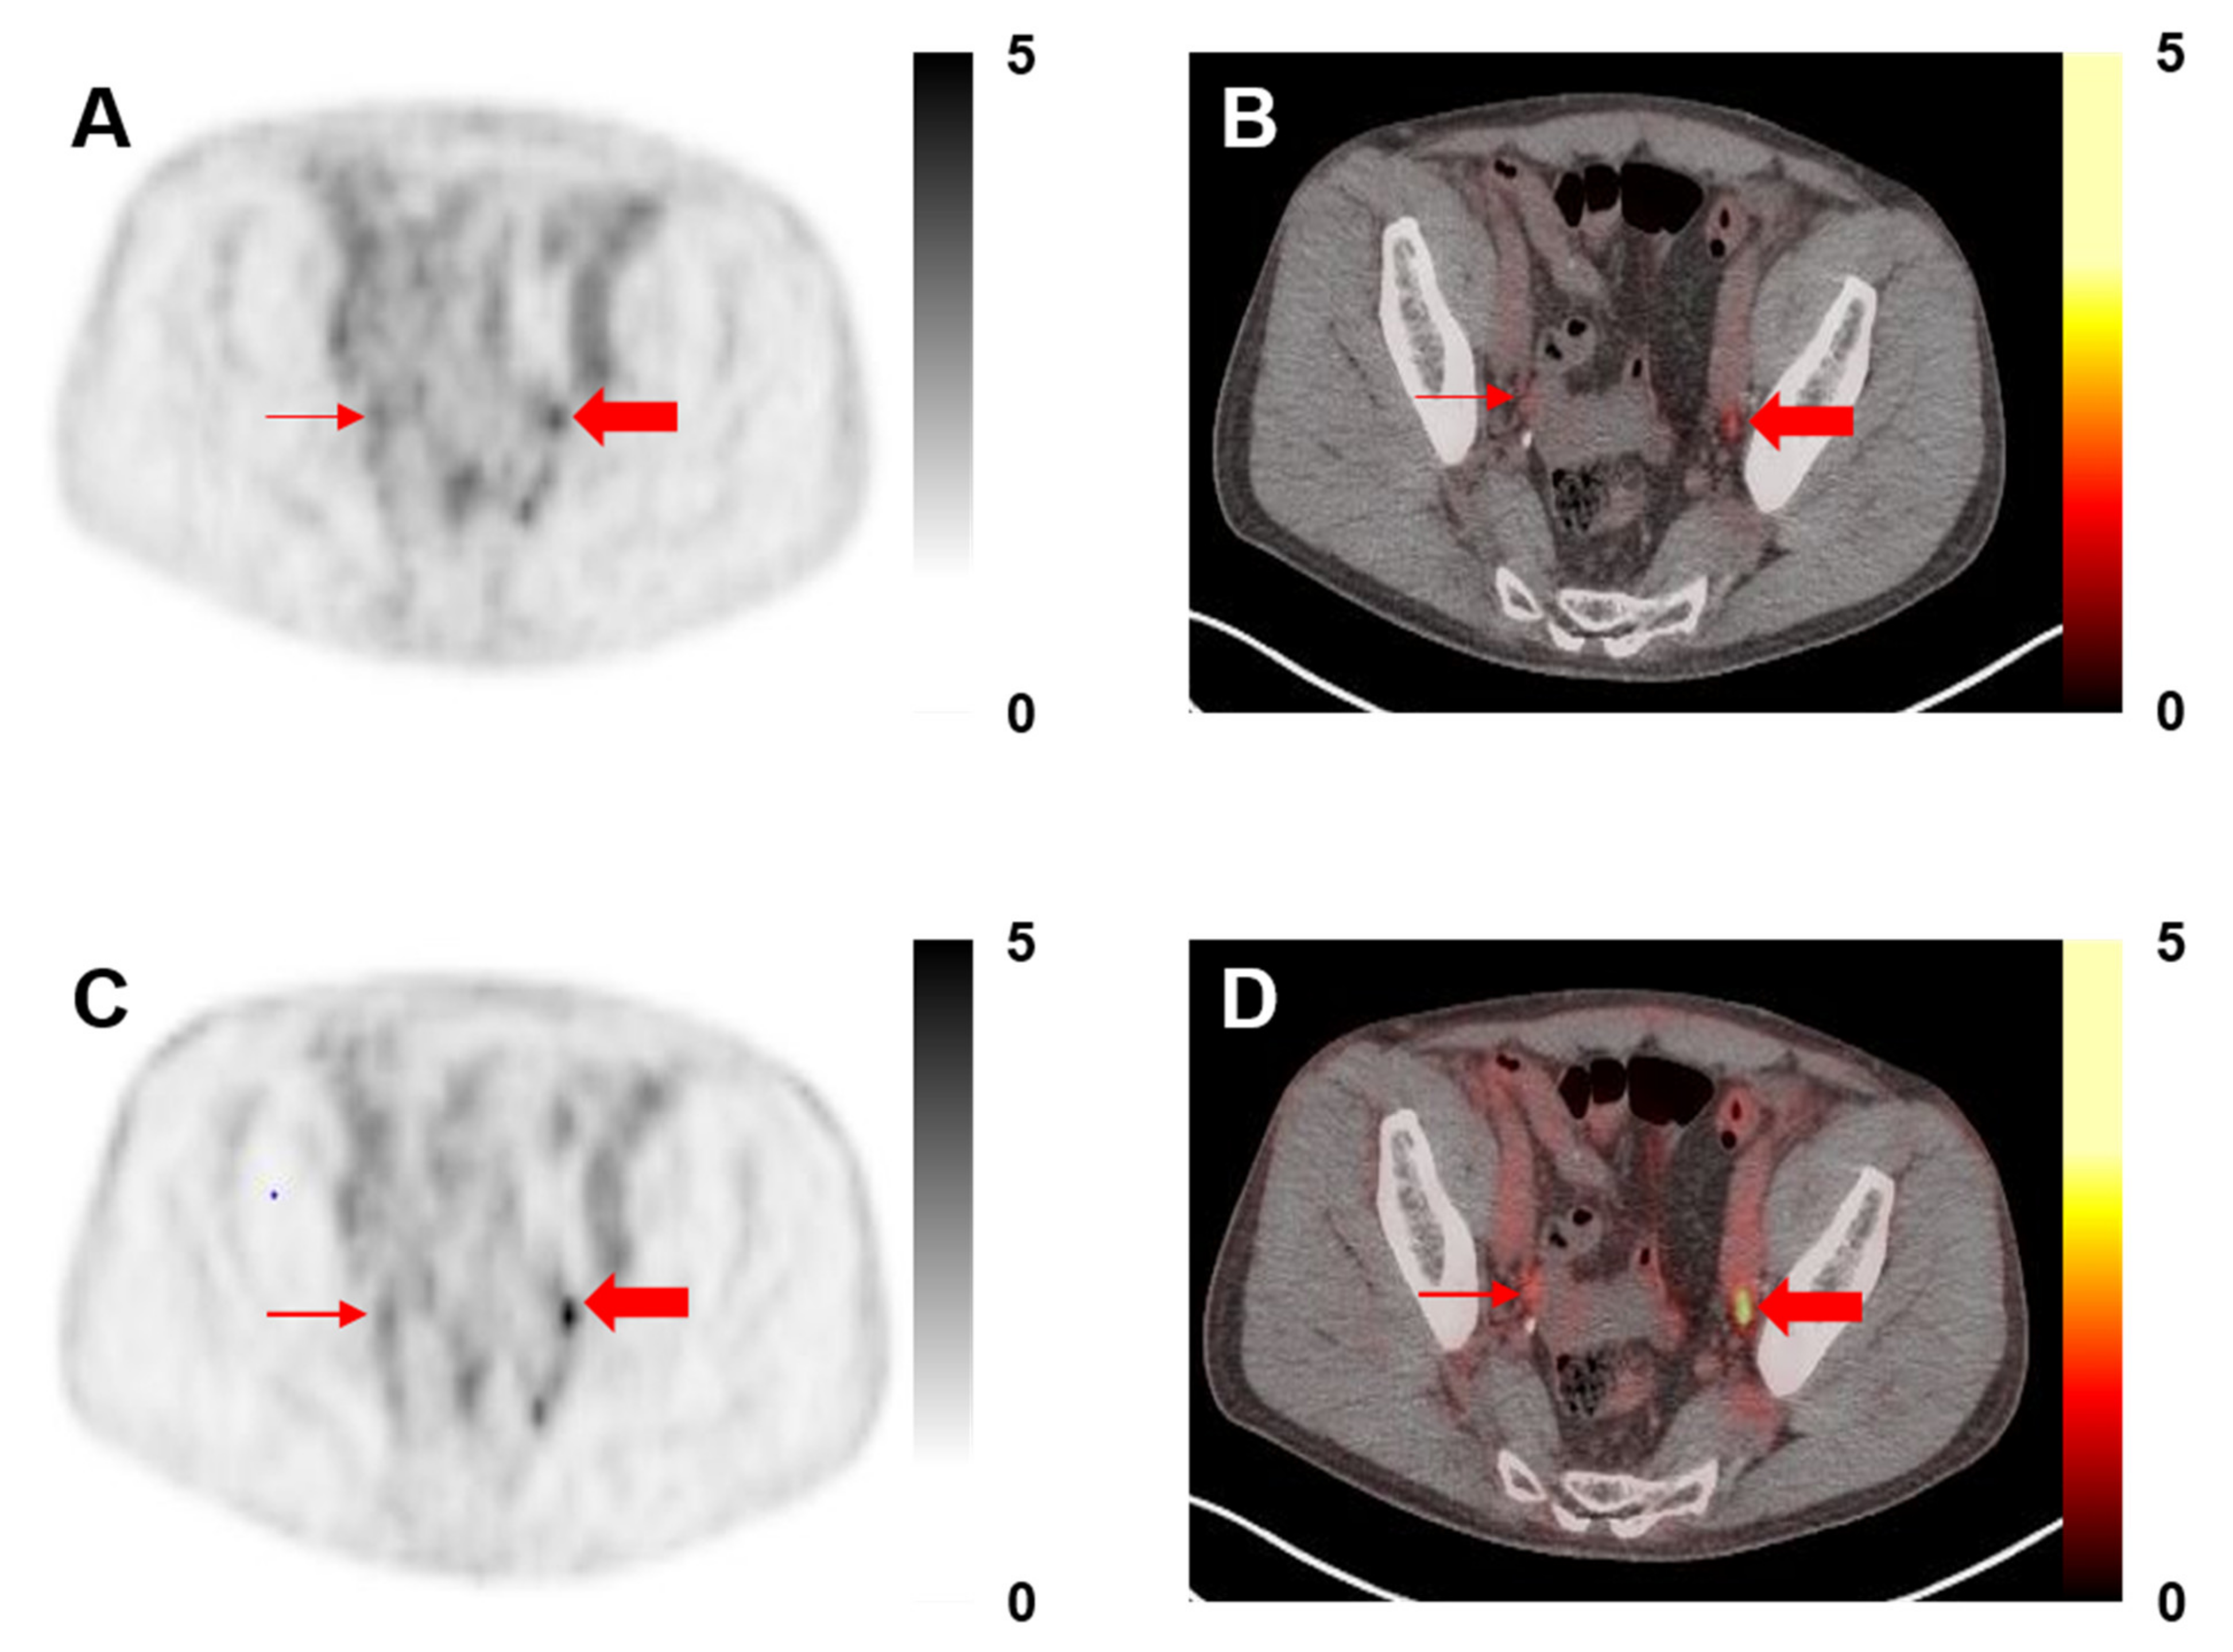

Among the 30 patients included in this study, a total of 171 lesions were designated as PSMA-RADS-3A (median 4 per patient, range 1–23), all of which were lymph nodes. Of these lesions, 13/171 (7.6%) demonstrated visual changes with PSF reconstructions such that they were re-categorized as PSMA-RADS-4 (Figure 1). A total of 112/171 (65.5%) lesions were found on follow-up imaging to be indicative of PCa, 32/112 (28.6%) by category 1 above, and 80/112 (71.4%) by category 2 above. A total of 13/13 (100.0%) of the re-categorized lesions were found to be true positive on follow-up imaging, whereas 99/158 (62.7%) lesions that were still considered indeterminate on the PSF reconstructions were found to be true positive on follow-up.

Figure 1. A 68-year-old man with history of prostatectomy and adjuvant chemohormonal therapy, now with an increase in prostate-specific antigen (PSA) to 0.3. (A) 18F-DCFPyL positron emission tomography (PET) and (B) PET/computed tomography (CT) axial images without point-spread function (PSF) demonstrating bilateral PSMA-RADS-3A pelvic lymph nodes (thin and thick red arrows, maximum standardized uptake value (SUVmax) 1.2 on the right and 1.5 on the left). (C) 18F-DCFPyL PET and (D) PET/CT axial images with PSF show that the right pelvic PSMA-RADS-3A lymph node does not appear significantly more conspicuous (SUVmax 2.2) and that lesion was not re-categorized. However, the lymph node on the left (SUVmax 2.5) was thought to be more conspicuous and was re-categorized to PSMA-RADS-4.